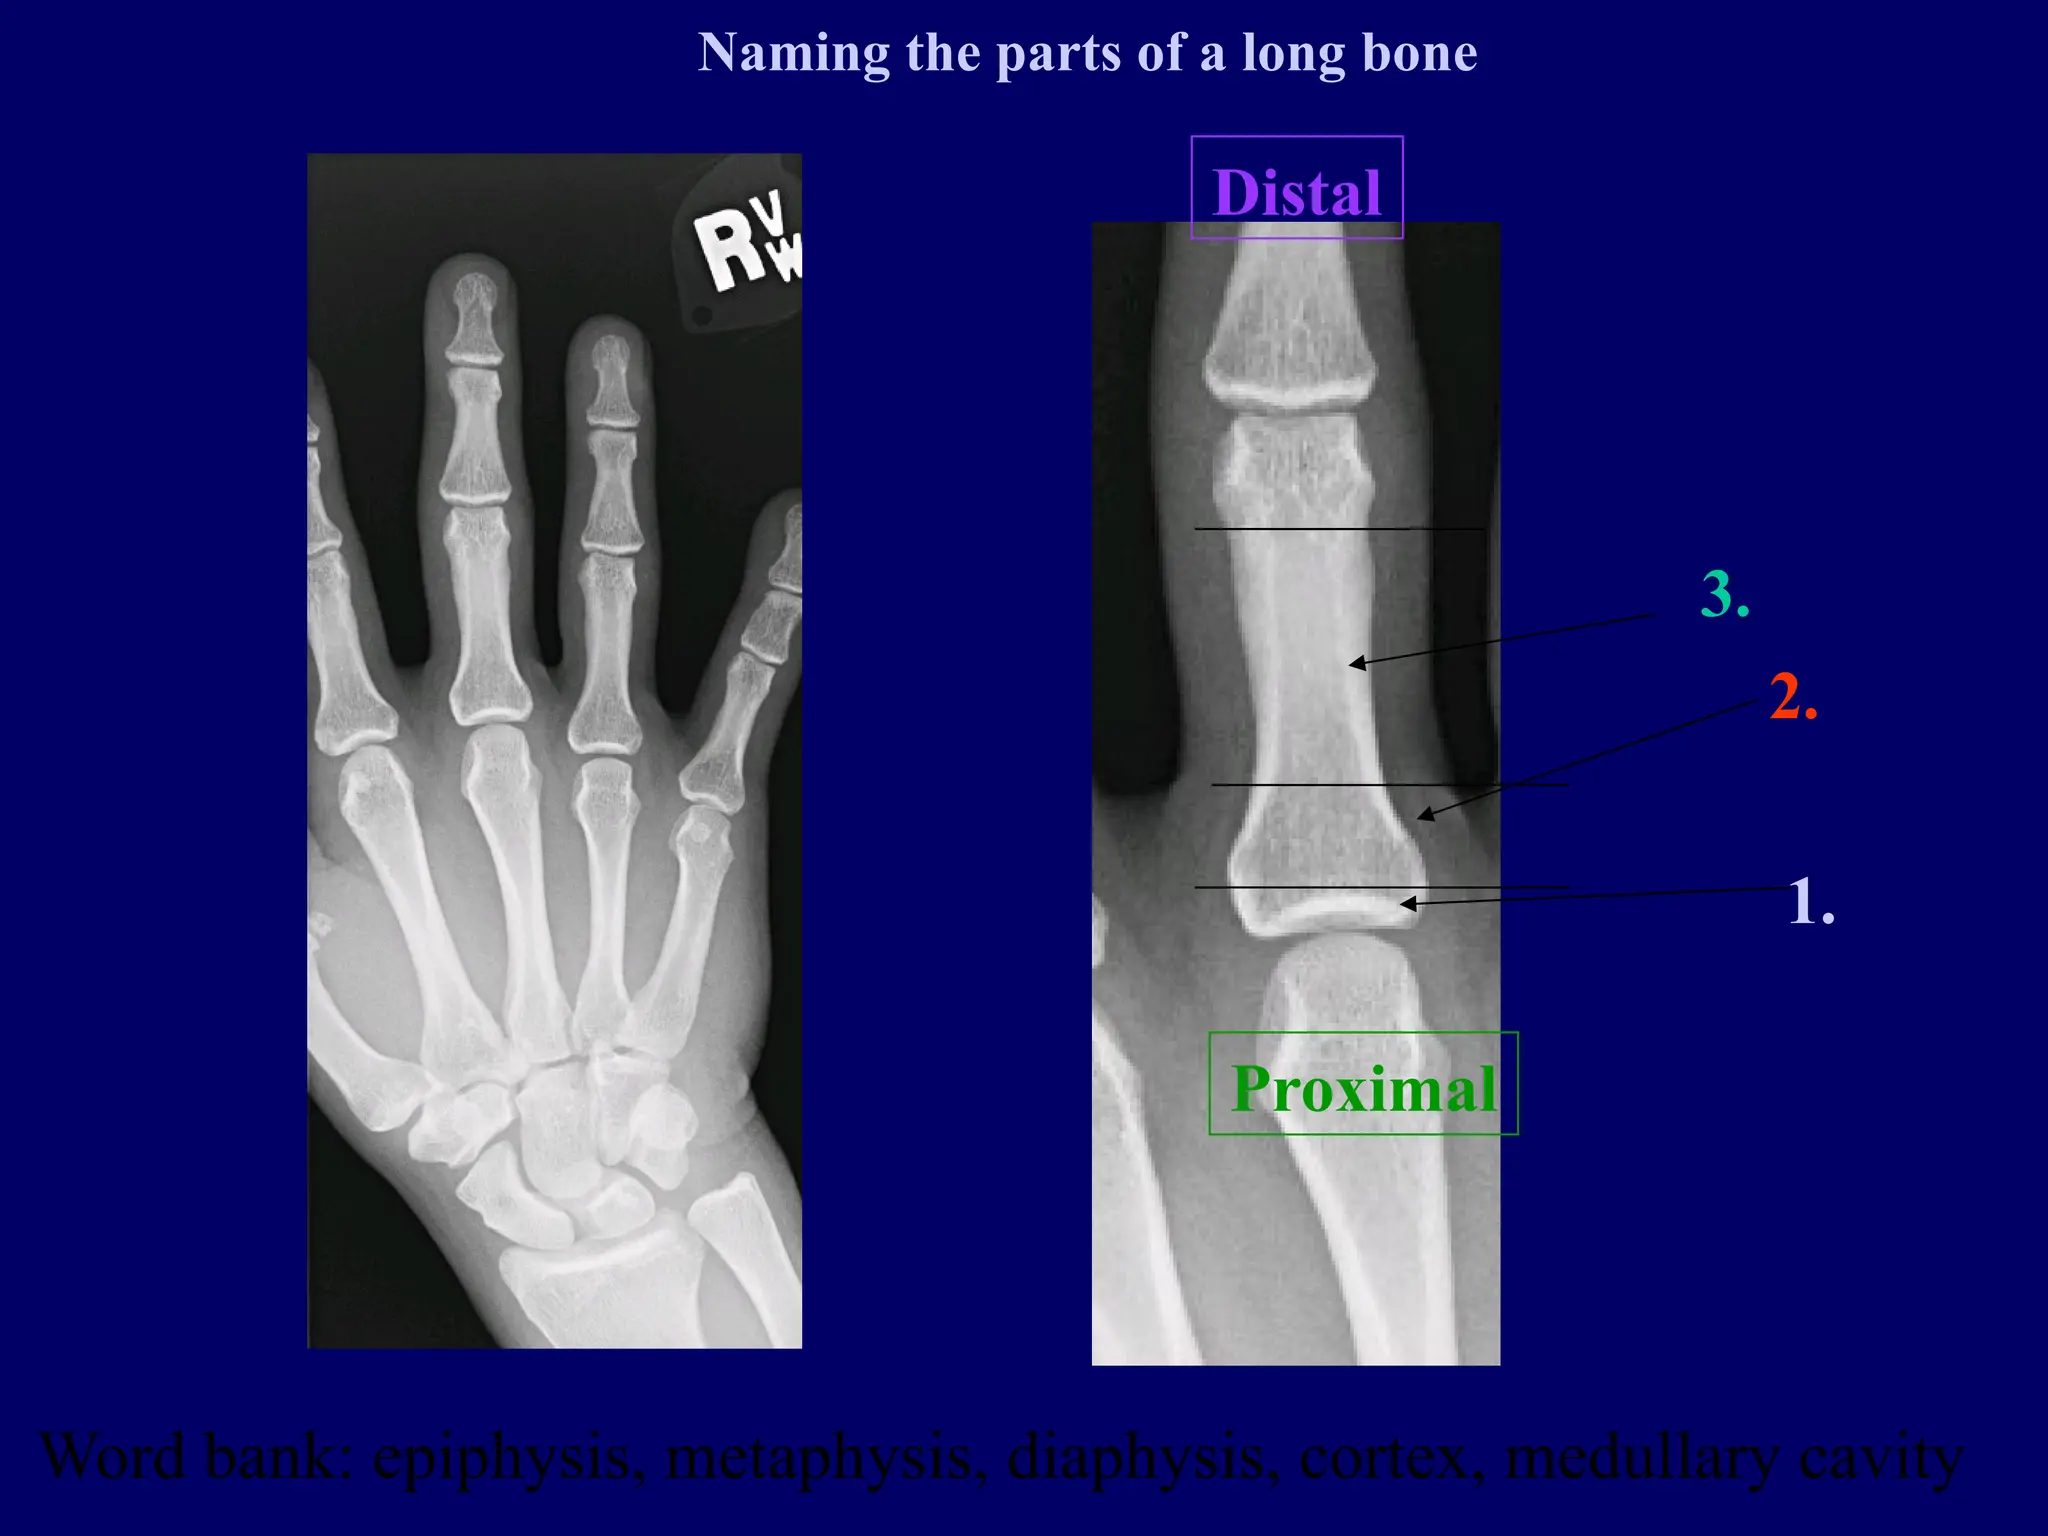

Word bank: epiphysis, metaphysis, diaphysis, cortex, medullary cavity

Naming the parts of a long bone

Proximal Distal 1. 2. 3. Word bank: epiphysis,metaphysis, diaphysis, cortex, medullary cavity Naming the parts of a long bone